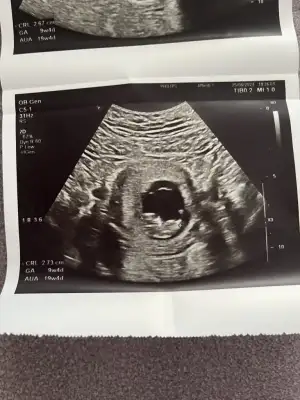

Bana da bakar mısınız kızlar cinsiyet tahmini neye göre yapılıyor . Birde bebeğin kafası neresi şu çıkıntılar elleri mi ya anlamadım![]()